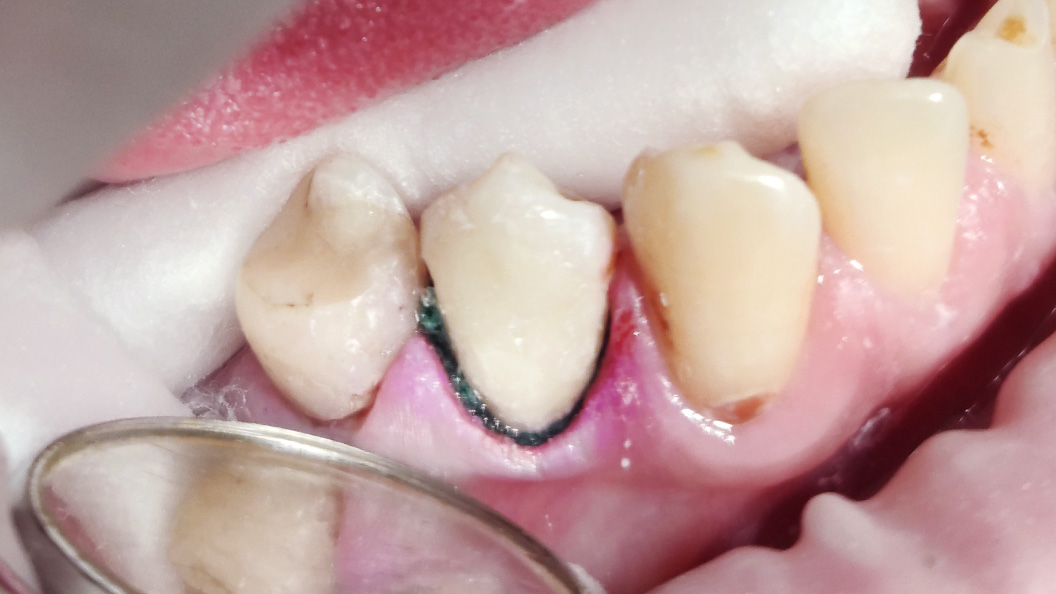

Пациент обратился с жалобой на эстетический недостаток в области нижнего зуба справа. После обработки кариозной полости врач выявил глубокий кариес. Дно и стенки полости плотные, гладкие, блестящие, при зондировании крепетируют. Реакция на холод слабоболезненна, на перкуссию — безболезненна. Диагноз — хронический глубокий кариес.

Ход лечения:

- введение анестезии Sol. Articaini vs. Adrenalini 1:200000 1.8 ml;

- наложение системы OptaGate;

- установка ретракционной нити UltraPack 00;

- механическая обработка кариозной полости;

- медикаментозная обработка полости раствором хлоргексидина 2%;

- пломбирование Vitremer (A3);

- микроконтурирование и макроконтурирование пломбы.